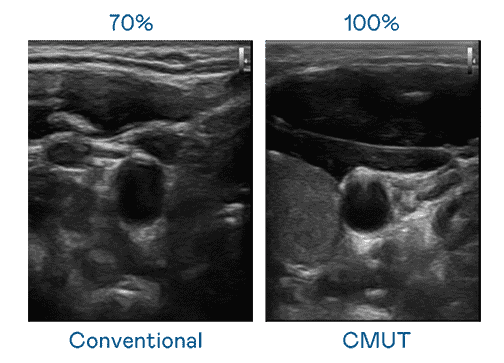

CMUT 技术是一种用电容式微机电元件来产生超音波讯号的技术。。与传统 PZT 压电式技术相比,,,CMUT 频宽增加 30%,,更宽频的超音波讯号让影像解析度大幅提升,,,是实现高影像品质医疗超音波扫描、、、、促进精准医疗发展的关键技术。。。

大频宽带来超清晰影像

超音波影像的解析度高低,,,首先取决于探头能发出的讯号频宽。。。。888.BY集团电子游戏 CMUT 可提供高清晰的超音波讯号,,,,提供高频宽、、、高灵敏度、、、影像纹理细节更高的超音波影像,,,,协助医护人员缩短影像判读时间及利用精准的医疗影像进行诊断。。。。